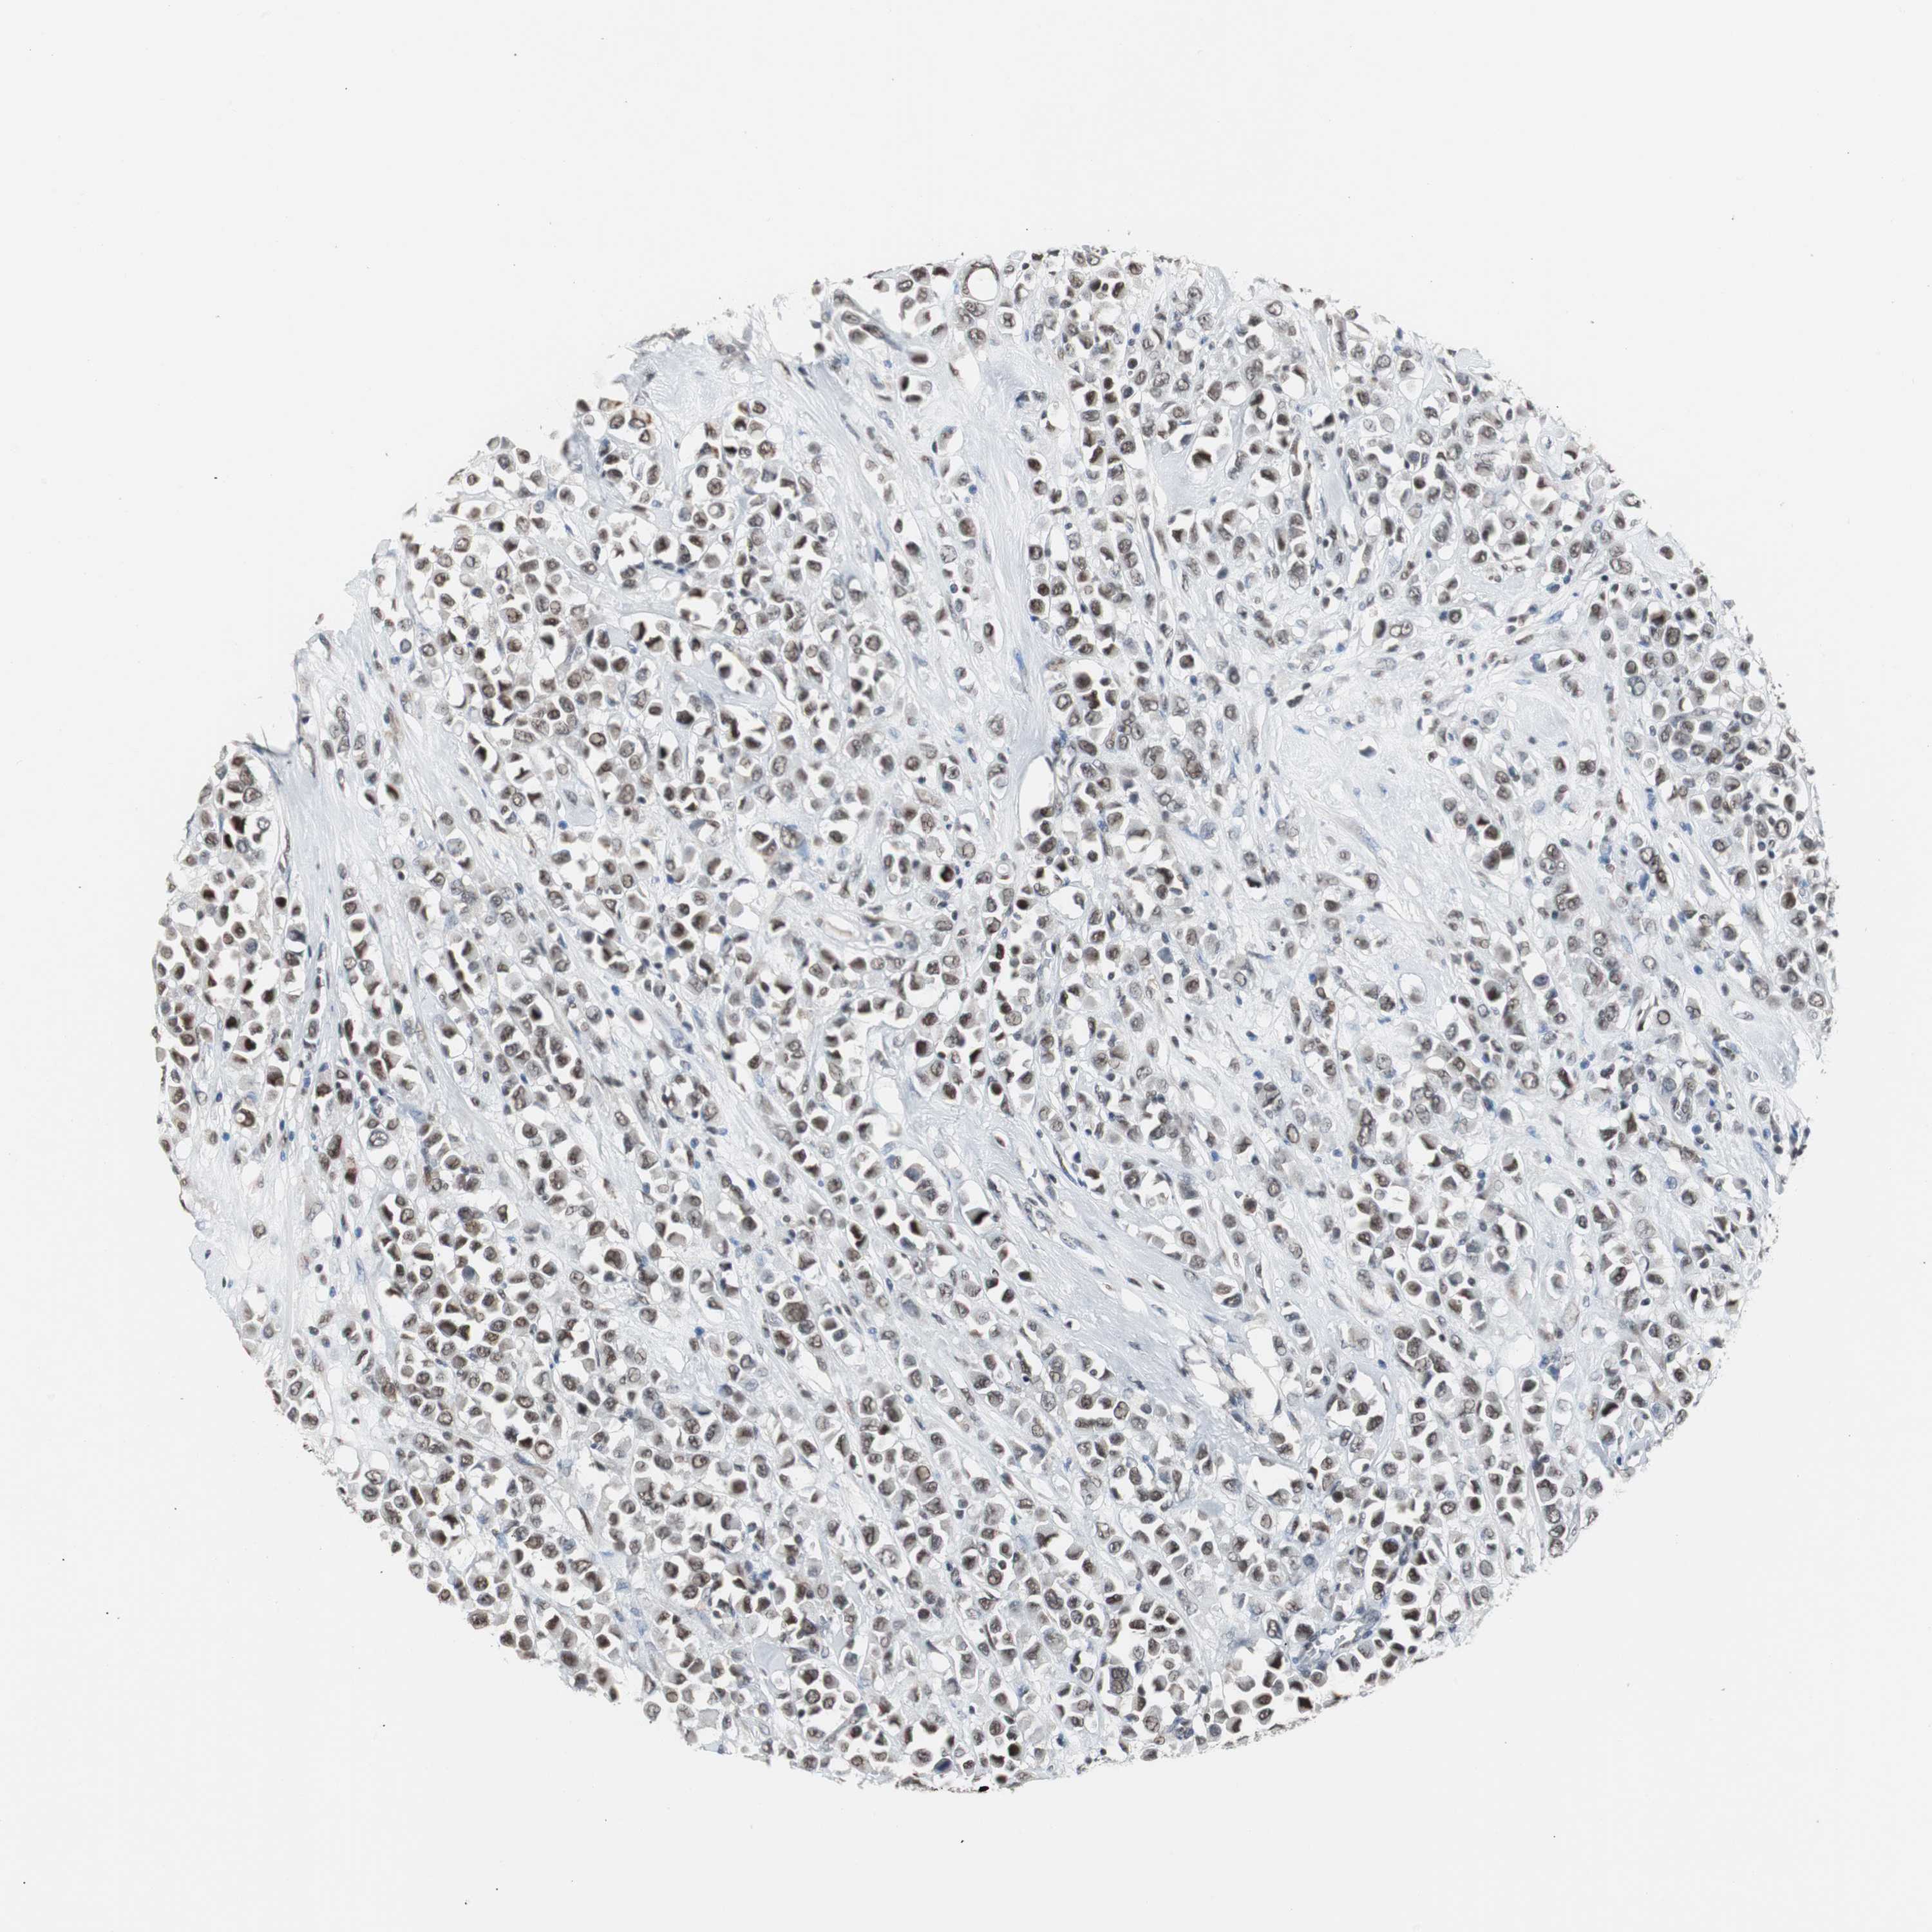

CANCER BREAST CANCER Show tissue menu

BRCA TCGA BRCA VALIDATION PROTEIN EXPRESSION